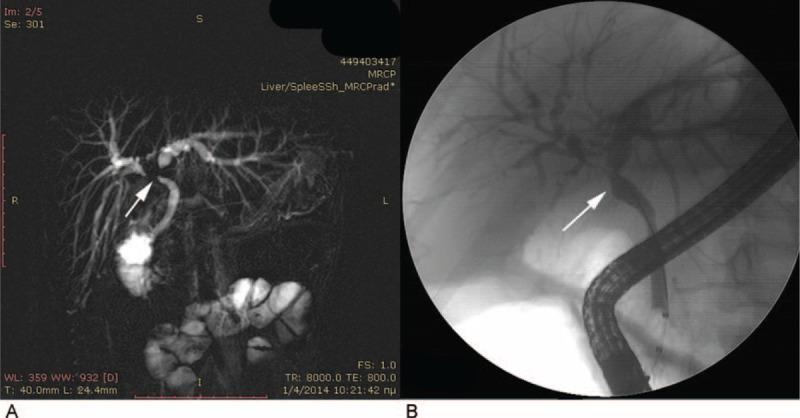

面对胆管狭窄时,必须仔细考虑良性和恶性病因,因为多种良性胆管狭窄可能会伪装成肝门部胆管癌(CCA)。因此,尽管可能是良性胆道疾病,患者仍可能接受大手术。在因疑似胆道恶性肿瘤而接受手术切除的患者中,约15%至24%会有良性病理结果。嗜酸性胆管炎(EC)是一种罕见的胆道良性疾病,可导致梗阻性黄疸,并且可能带来诊断难题。我们报告一例罕见病例,一名年轻女性因肝内胆管汇合处胆管狭窄导致梗阻性无痛性黄疸被转诊至我院,初步诊断为胆管癌。然而,在检查过程中发现她患有EC,这是一种极其罕见的胆管狭窄良性病因,其特征是胆管树有密集的嗜酸性粒细胞浸润,导致狭窄、纤维化和梗阻,并且短期高剂量使用类固醇激素可使其逆转。尽管EC罕见,但当影像学检查显示胆管狭窄时,尤其是在无法做出术前恶性肿瘤诊断、存在外周嗜酸性粒细胞增多且无恶性肿瘤主要症状的情况下,应考虑到EC。